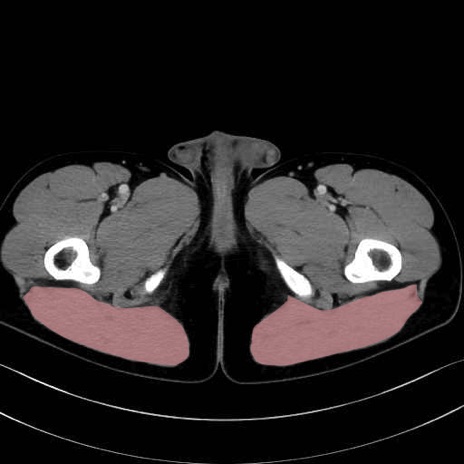

大殿筋 (Gluteus maximus)